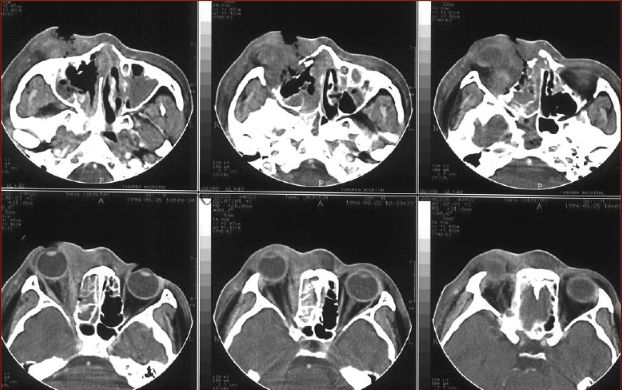

慢性多发鼻窦炎鼻息肉

慢性多发鼻窦炎—MRI